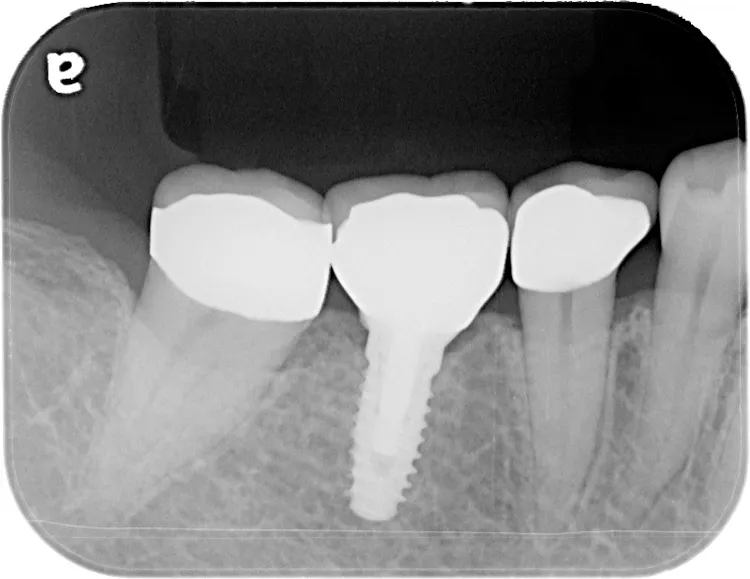

治療内容

左下67 欠損に対してインプラント治療を行った症例

部分床義歯を使用していたが、どうしても慣れない上にしっかり噛むことができないためインプラント治療を希望